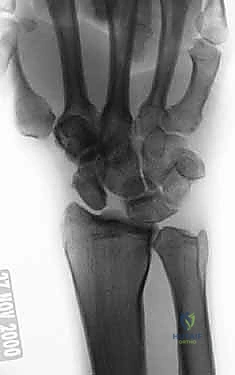

* SLIL Exposure: With the capsule opened, we now have direct visualization of the scaphoid, the lunate, and the disrupted scapholunate interosseous ligament. Observe carefully for any existing arthritic changes in the radiocarpal and midcarpal joints, as well as the precise location of the SLIL disruption. Typically, the SLIL avulses off the scaphoid, leaving a stump attached to the lunate. Also, assess for any injury to the DIC ligament, which can sometimes avulse from its scaphoid and lunate attachments in high-energy injuries.

* Observe the flexed scaphoid (S) and the extended lunate (L), characteristic of a DISI deformity. The capitate (C) is visible distally. Note the complete disruption of the SLIL. The arrow points to our ulnar-based capsular flap.

* Here, you can clearly see the scaphoid on the left, and the SLIL stump still attached to the lunate on the right, held by the forceps. The capitate head is distal to the lunate.